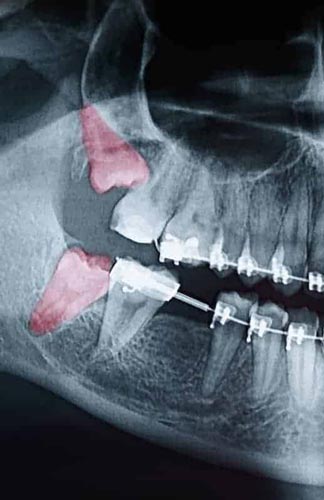

Most people’s mouths only have enough room for 28 teeth. When your wisdom teeth start to come in, that’s four additional teeth trying to cram their way in. In the majority of situations, this creates a litany of problems, including crowding, soreness, risk of infection, and the need for extraction. Since your wisdom teeth are the last teeth to erupt through your gums, they come to the party a little late. All your other teeth have settled into their places. With x-rays and inspections, we can determine if your wisdom teeth are impacted and need to be removed.

Though some patients may not require the removal of their wisdom teeth, most often, it’s needed to protect your overall oral health. Wisdom teeth can begin to grow in sideways, only partially erupt, or even get stuck beneath the gum and bone. Known as impacted teeth, those that get stuck may resort to shifting positions as they try to find a pathway for eruption. When wisdom teeth don’t erupt through the gumline properly, they can create severe problems for the patient, including:

To evaluate the state of your wisdom teeth, we’ll first do a thorough examination and take x-rays of your mouth. This will help us determine if your wisdom teeth pose a current or future threat to your oral health. Early detection of issues results in better outcomes for our patients, so we recommend the first evaluation be completed in a patient’s mid-teenage years.

An impacted tooth simply means it is “stuck” and cannot erupt into function. Patients frequently develop problems with impacted third molars, also known as wisdom teeth. These teeth get “stuck” in the back of the jaw and can develop painful infections among a host of other problems. Since there is rarely a functional need for wisdom teeth, they are usually extracted if they develop problems.

Normally, maxillary canines are the last “front” teeth to erupt into place. They usually come into place around age 12 and cause any space left between the upper front teeth to close tighter together. If a canine gets impacted, every effort is made to get it to erupt into its proper position in the dental arch. The techniques involved to aid eruption can be applied to any impacted tooth in the upper or lower jaw, but most commonly are applied to maxillary canine (upper eye) teeth. Sixty percent of these impacted eyeteeth are located on the palatal (roof of the mouth) side of the dental arch. The remaining impacted eye teeth are found in the middle of the supporting bone but stuck in an elevated position above the roots of the adjacent teeth or out to the facial side of the dental arch.